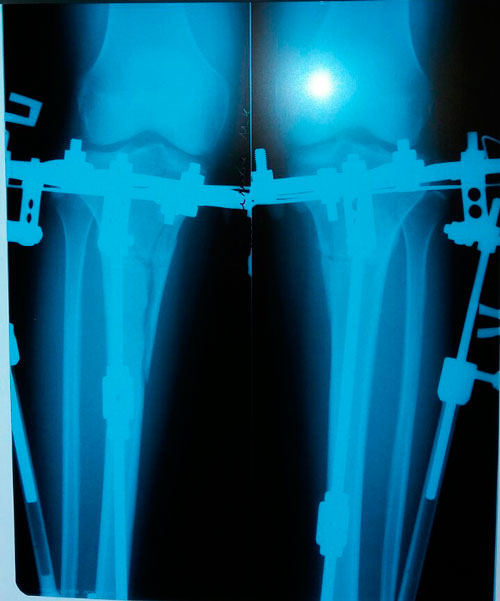

рентген в процессе исправления деформации

в процессе исправления ротации